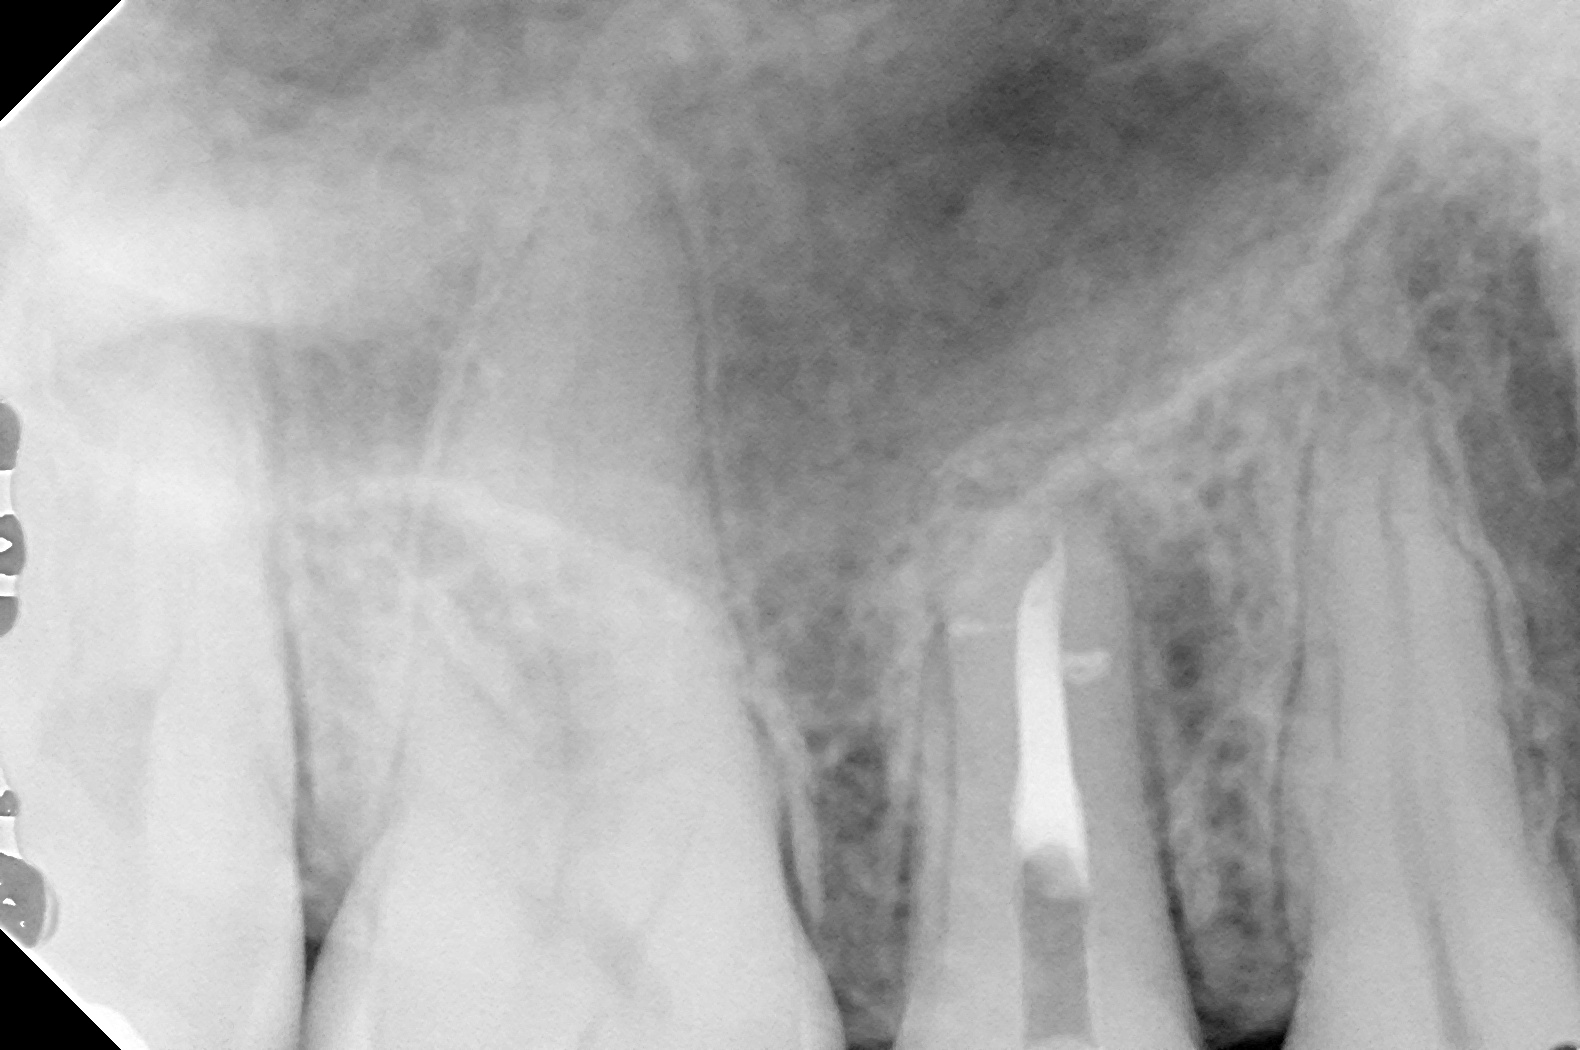

膿の出口から充填剤を入れてみると根の先に向かって入っていきましたので、根の治療をしてみると

横にびゅっと何かが入ってます。

これは側枝と呼ばれており、神経の管には先端3ミリでほとんどの歯に側枝があると言われております。